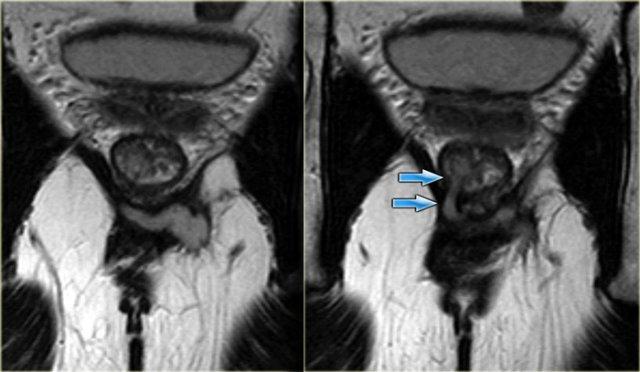

Bên trái là hình ảnh coronal của một bệnh nhân khác có rò liên cơ thắt.

Bên trái là hình ảnh coronal chuỗi xung T2W của một ổ áp xe nhỏ trong hố ngồi-hậu môn trái, đường rò chạy xuyên qua cơ nâng hậu môn.

Do đó, đường rò nằm phía trên phức hợp cơ thắt và thuộc loại ngoài cơ thắt.